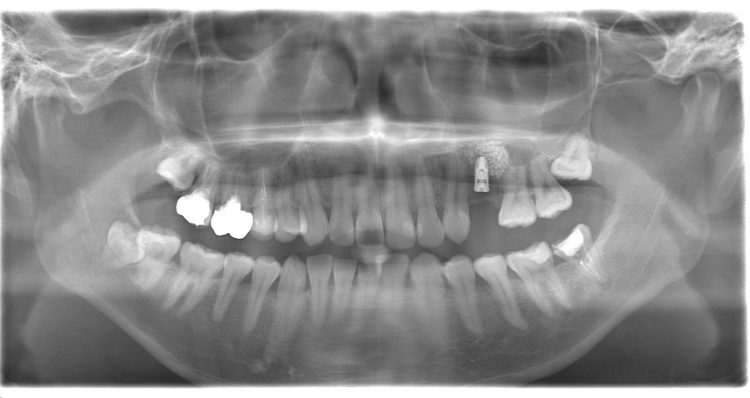

左上の4番目、5番目の歯並びが悪く、重なり合ってしまい大きな虫歯になっていました。

2本とも抜歯し、インプラントを入れることになりました。

今回は骨を増やすためのサイナスリフトという処置も併用して、一定以上の長さのインプラントを入れられるようにしました。

<初診時>

<抜歯後・オペ前>

<オペ後>

オペ後は腫れもあまりなく、経過良好でした。